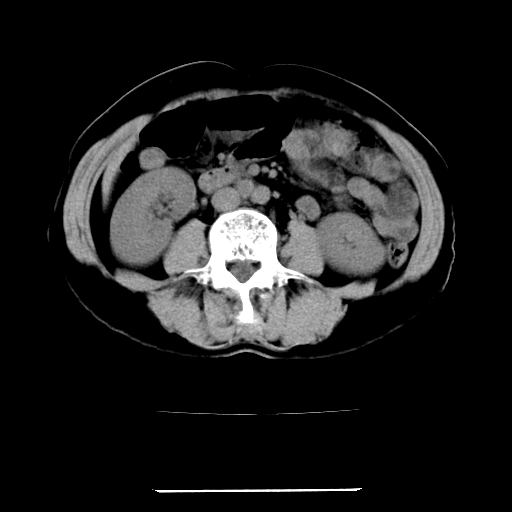

标题: CT22301:女,67岁,上腹部疼痛一周伴皮肤黄染,无发热。 [打印本页]

女,67岁,上腹部疼痛一周伴皮肤黄染,无发热。

左叶肝内胆管结石,并远端肝内胆管扩张。

考虑:肝内胆管结石继发肝内胆管扩张,右肾旋转不良。

肝内外胆管结石并肝内胆管扩张。

肝内外胆管扩张,左叶胆管内结石

1、肝门高密度影下层面和胰头层面可见轻度胆管扩张,而静脉和延迟期均未见扫描完胰头,不能完全排除胰头占位。2、肝门部高密度影,考虑钙化或结石。

考虑肝门胆管癌伴门脉左支受侵包埋,建议mrcp进一步检查。